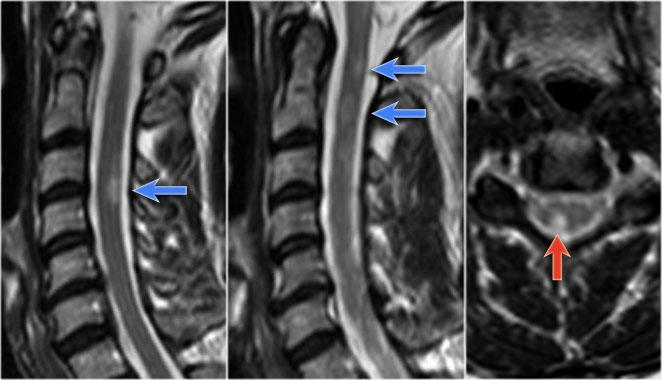

Trên hình ảnh cắt ngang, các tổn thương MS thường có hình tròn hoặc hình tam giác và nằm ở phía sau hoặc phía bên.

Vậy chúng ta có thể loại trừ MS nếu tổn thương nằm ở phía trước không?

Tiếc là không thể.

MS là bệnh “bắt chước vĩ đại” và cũng có thể nằm ở phía trước như ở bệnh nhân này, người có tổn thương ở vị trí điển hình (mũi tên xanh) nhưng cũng có tổn thương ở phía bụng của tủy (mũi tên đỏ).

Điều này không phổ biến, nhưng bạn không thể loại trừ MS.

Khi các tổn thương MS đang hoạt động, chúng có thể ngấm thuốc, nhưng sự ngấm thuốc không phổ biến như ở não.

Các kiểu ngấm thuốc không đặc hiệu.

Có thể thấy ngấm thuốc dạng vòng nhẫn, ngấm thuốc mạnh và ngấm thuốc nhẹ.

Kiểu ngấm thuốc nhẹ hoặc mờ nhạt là phổ biến nhất.

Đây là hình ảnh của bệnh nhân MS lâu năm đang trong đợt cấp.

Có sự ngấm thuốc ở các tổn thương đang hoạt động.

Tiếp tục xem các hình ảnh của cột sống cổ.

Trong tủy sống cũng có nhiều tổn thương.

Trên hình ảnh cắt ngang thấy một tổn thương phía lưng hình tam giác điển hình.

Tiếp tục xem các hình ảnh sau tiêm thuốc tương phản từ.

Ở tủy sống cũng có nhiều tổn thương MS ngấm thuốc.